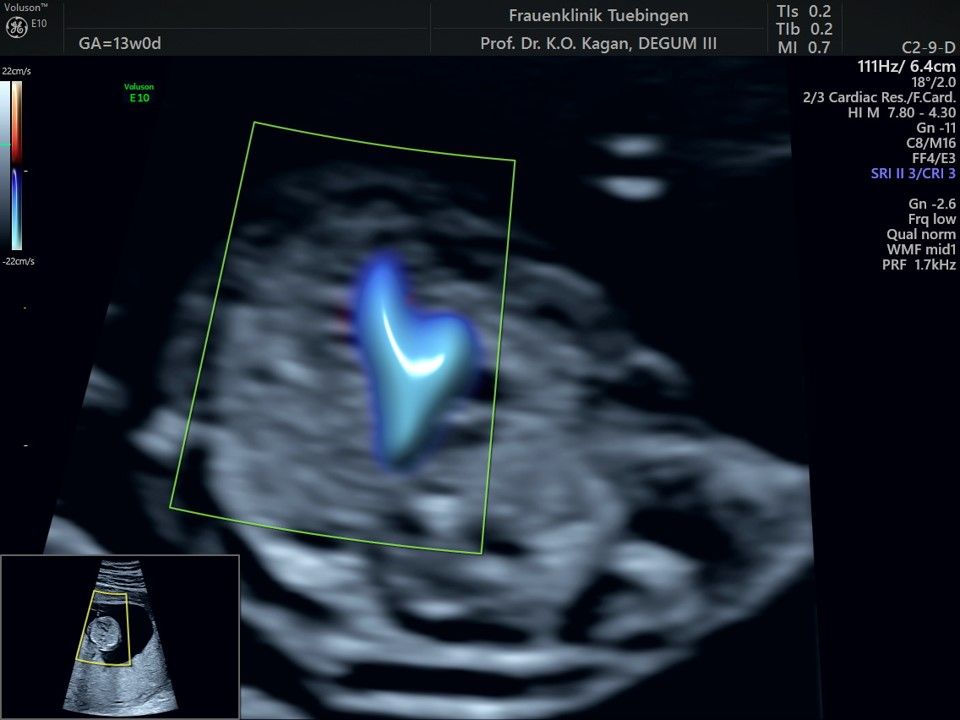

Das Ergebnis der Ultraschalluntersuchung ist wegweisend. Dabei wird der Fet vermessen, die Organe werden untersucht und die sonographischen Marker zur Risikoberechnung für Chromosomenstörungen werden beurteilt. Das sind: die Nackentransparenzdicke, Nasenbein sowie der Blutfluss in der rechten Herzhälfte und im Ductus venosus, einem Gefäß in der Leber des Feten.